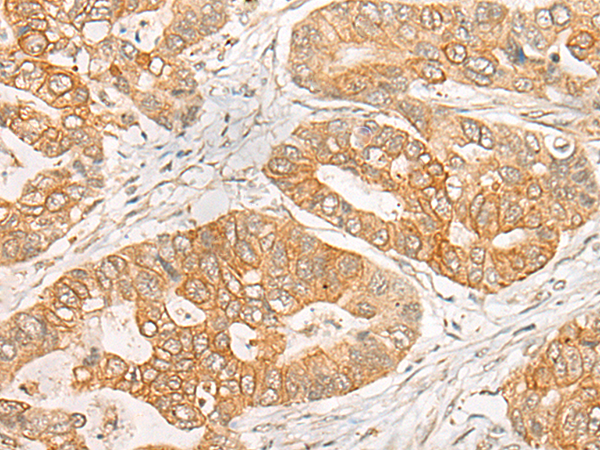

分类: 科研抗体货号: P06327别名: PL; HOX1; HOX1H; HOX1.8应用: WB,IHC反应种属: Human, Mouse